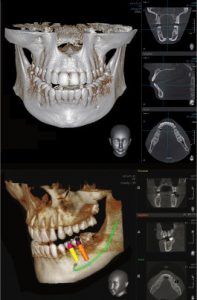

3D-Röntgen (DVT - Digitale Volumentomographie)

Die Praxis erstellt dreidimensionale Röntgenbilder, die eine besonders exakte Analyse und Visualisierung dentaler Strukturen ermöglichen. Knochen, Zähne und kleinste Nervenverläufe werden in ihrer räumlichen Umgebung dargestellt. Das dient einer detaillierten Diagnose, einer sicheren Operationsplanung und gegebenenfalls auch der Behandlungskontrolle.

Das 3D-Röntgen bedeutet für Sie mehr Sicherheit, schonendere Behandlungen und oft auch eine verkürzte Eingriffsdauer. Es kommt insbesondere bei der Implantatplanung, bei schwierigen Zahnentfernungen, Wurzelspitzenresektionen, Knochenaufbauten oder bei Wurzelbehandlungen zum Einsatz. Immer dann, wenn anatomische Strukturen besonders genau erkannt und sensible Bereiche wie Nerven geschützt werden müssen, bietet dieses Verfahren einen großen Vorteil.

3D-Darstellung eines Kiefers mit DVT-Aufnahmen